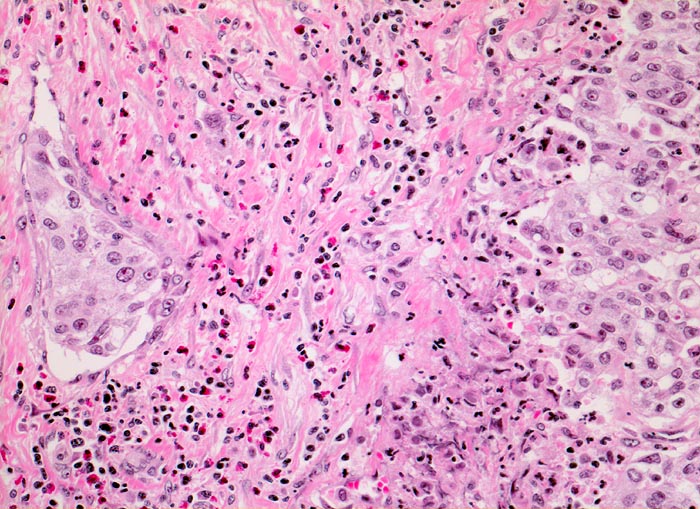

Morphologische Merkmale:

• Multiple Fragmente einer transurethralen Resektion.

• In der Mitte oben ist ein Harnblasenfragment mit tumorfreien Anteilen der Harnblasenwandmuskulatur erkennbar. Dieses Fragment ist bedeckt von einem aus wenigen Zellagen bestehenden dyskohäsiven Urothel, von dem sich einzelne Zellen ablösen. Die Zellkerne sind pleomorph, hyperchromatisch und vergrössert(Carcinoma in situ des tumorfernen Urothels).

• Fragmente eines papillär aufgebauten Karzinoms.

• Tumorzellkerne mit ausgeprägter Pleomorphie und Hyperchromasie sowie prominenten Nukleolen. Fehlende polare Ausrichtung der Tumorzellen. Zahlreiche Mitosen und Apoptosen.

• Kleinherdige Tumornekrosen.

• Invasion der Lamina propria (Tumorfragmente links): Kleine Tumorzellgruppen oder Einzelzellen haben die Basalmembran an wenigen Stellen durchbrochen und liegen in der Lamina propria.

• Begleitendes dichtes gemischtes Entzündungsinfiltrat.